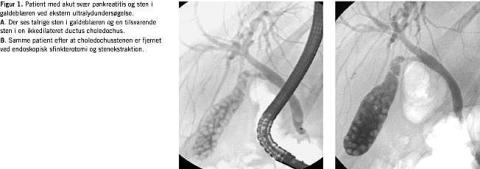

Der blev udført en omfattende litteratursøgning, som imidlertid ikke afslørede flere end de allerede kendte tre randomiserede studier, idet et polsk randomiseret studie, der er publiceret som abstrakt, og en italiensk case-kontrol-undersøgelse blev ekskluderet fra studiet. Det polske studie blev ekskluderet, fordi der var en anden indgang end den kliniske mistanke om GAP, og i det italienske var indgangen ikke randomiseret. Kun randomiserede kontrollerede forsøg med patienter over 15 år, som opfyldte kliniske og parakliniske kriterier for at have GAP, hos hvem ERCP blev udført inden for 72 timer efter indlæggelsen, og hvor mortalitet og komplikationer i forbindelse med pankreatitten var mål for effekten, kunne indgå i analysen. Et særligt problem var, at patienter med akut kolangitis blev behandlet forskelligt i de tre studier, man måtte derfor gennemføre en korrektion for den konfundering, som dette kunne give anledning til. Det britiske studie [3] og Hongkong-studiet [1] var fra et enkelt center, mens det tyske studie var en multicenterundersøgelse [2]. Ud over effekten i hele den korrigerede patientgruppe undersøgte forfatterne også effekten i undergrupper med forventet svær og med let pankreatitis, idet Ranson- eller modificeret Glasgow-score blev anvendt til forudsigelse af sværhedsgraden af forløbet (Figur 1 ).